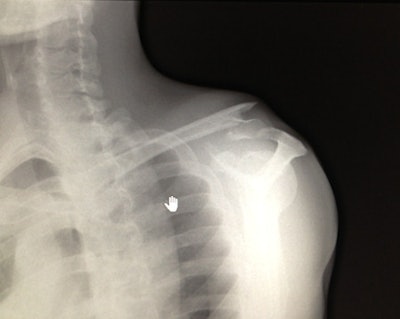

Each morning the bus would move to the next "arrival" point and throughout the day, as the riders trickled in, the team would treat injuries that ranged from fractures of the shoulder, wrist, finger, ankle, and foot, as well as tendinopathies and hematomas. Patients could be imaged, treated, and even put into plaster or stitched, all within the confines of the medical truck.